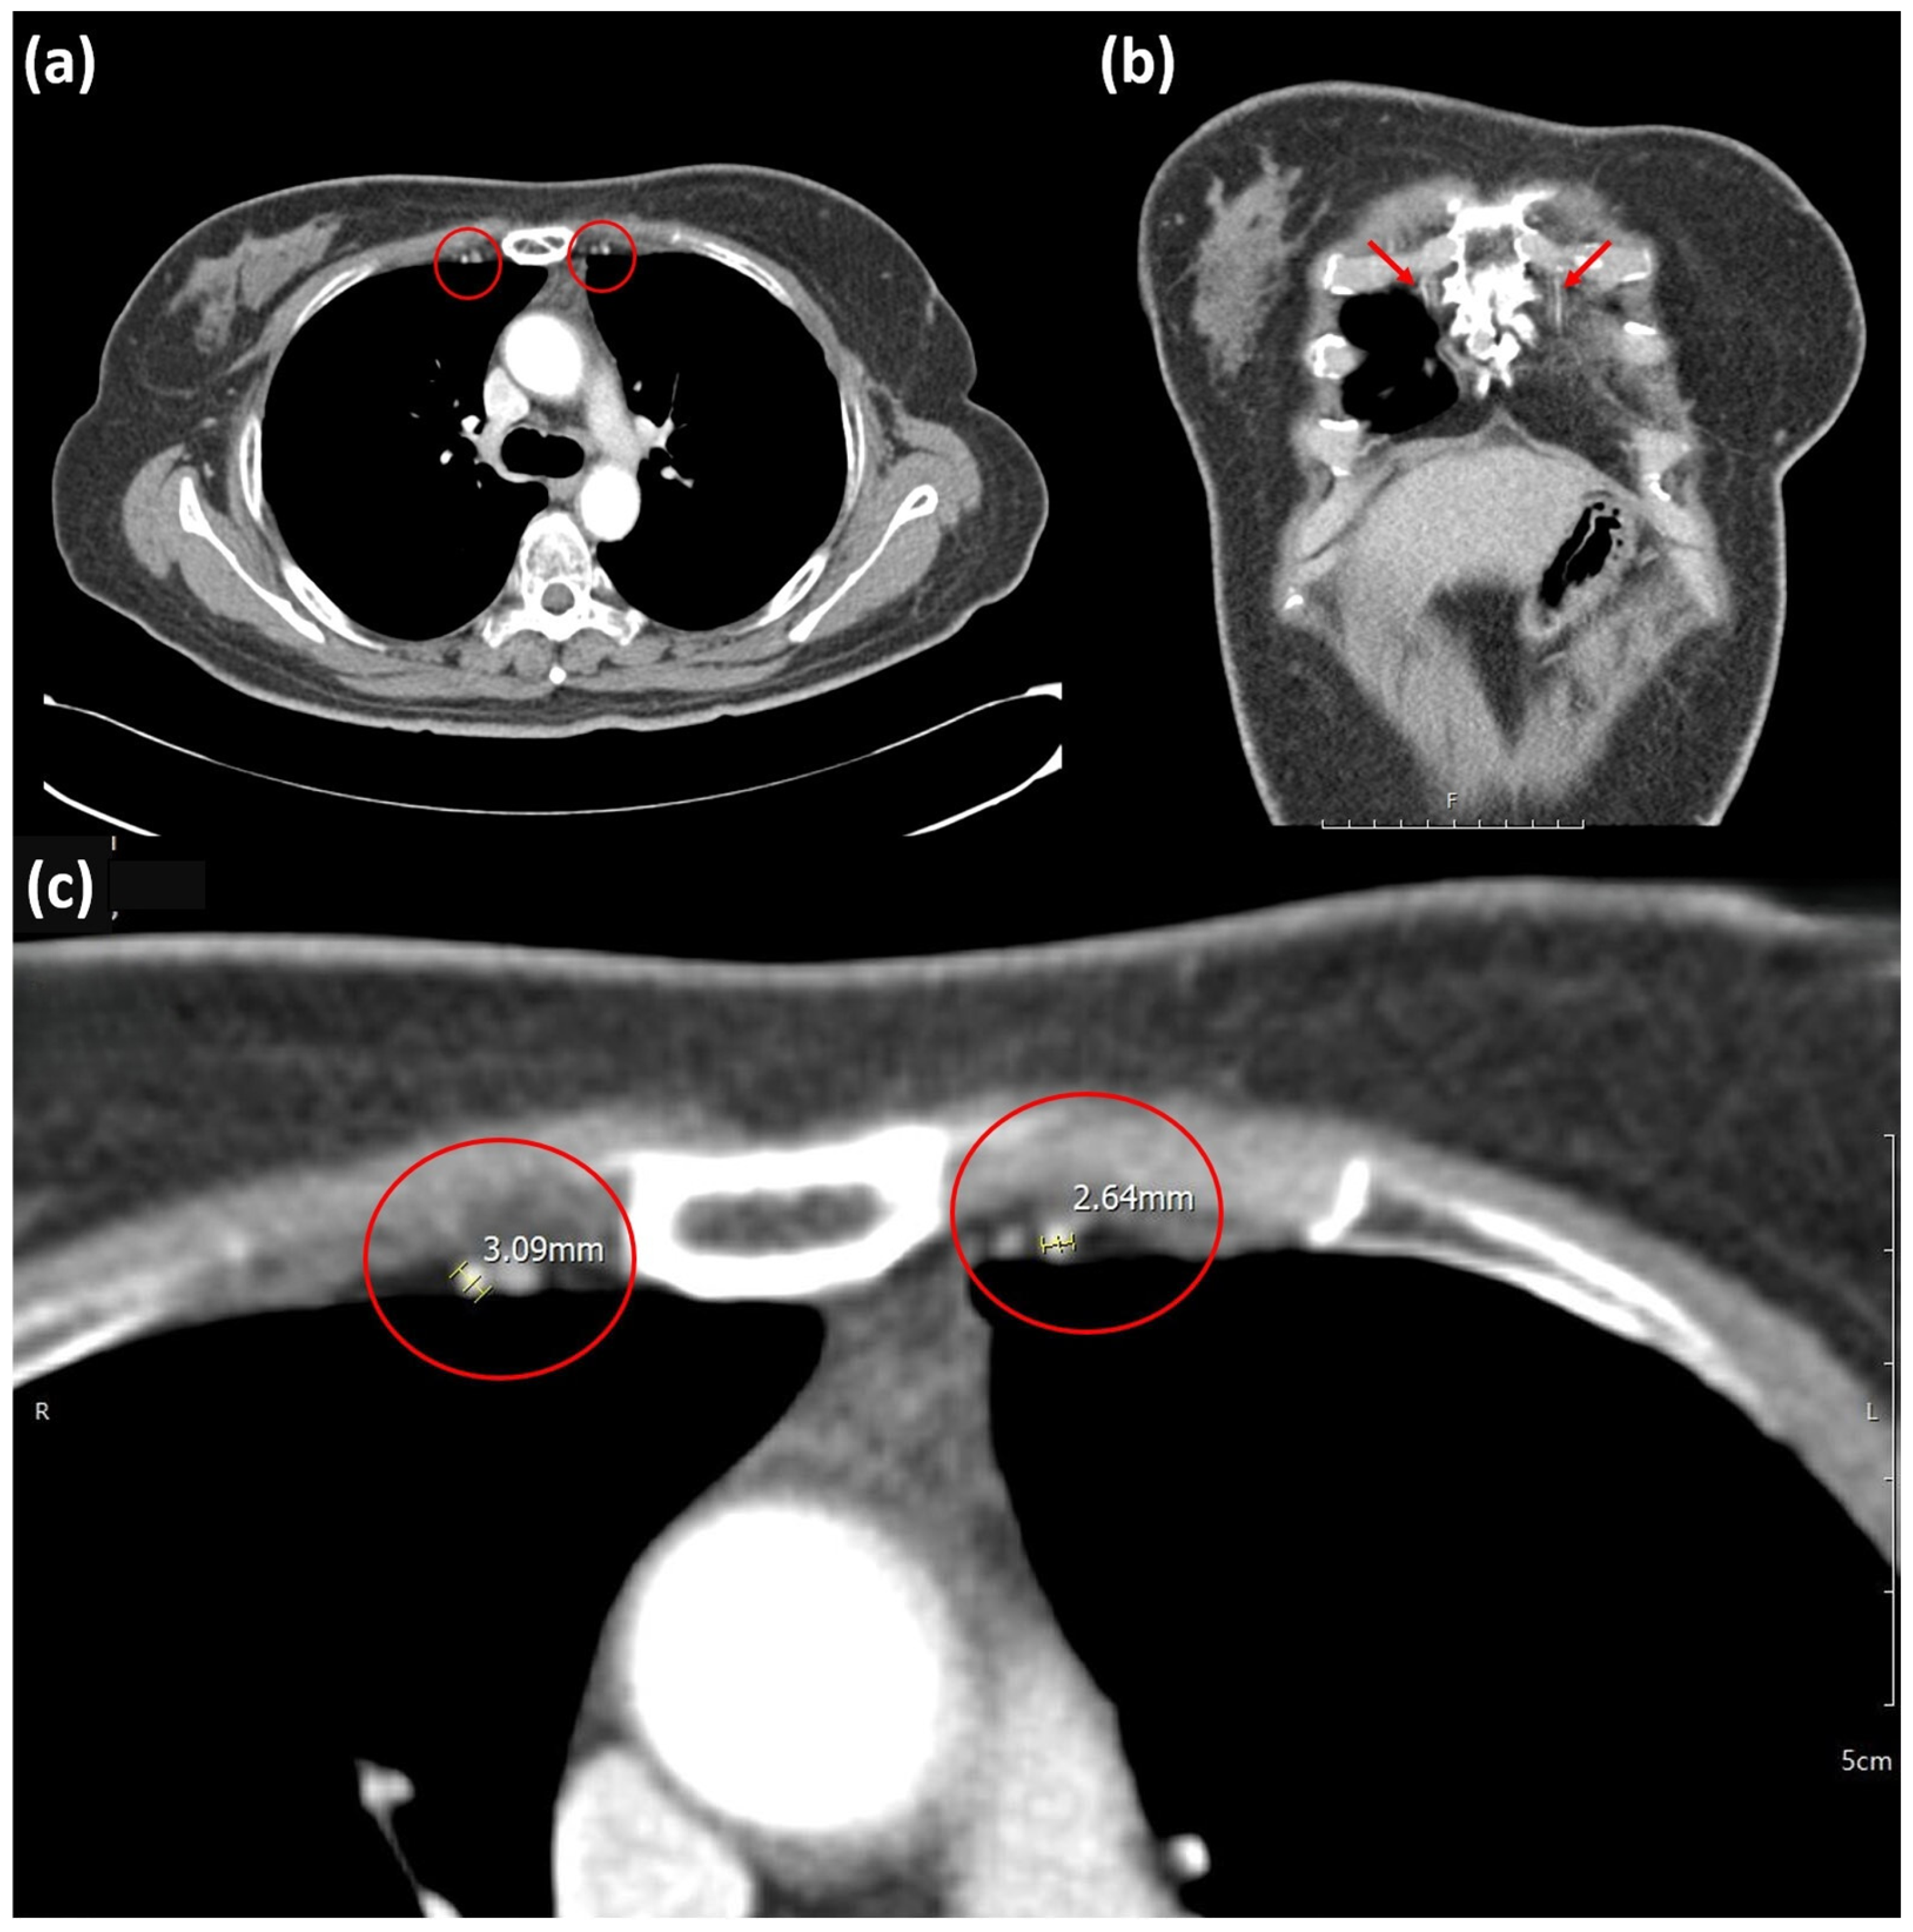

| TDA | Thoracodorsal artery |

| IMA | Internal mammary artery |